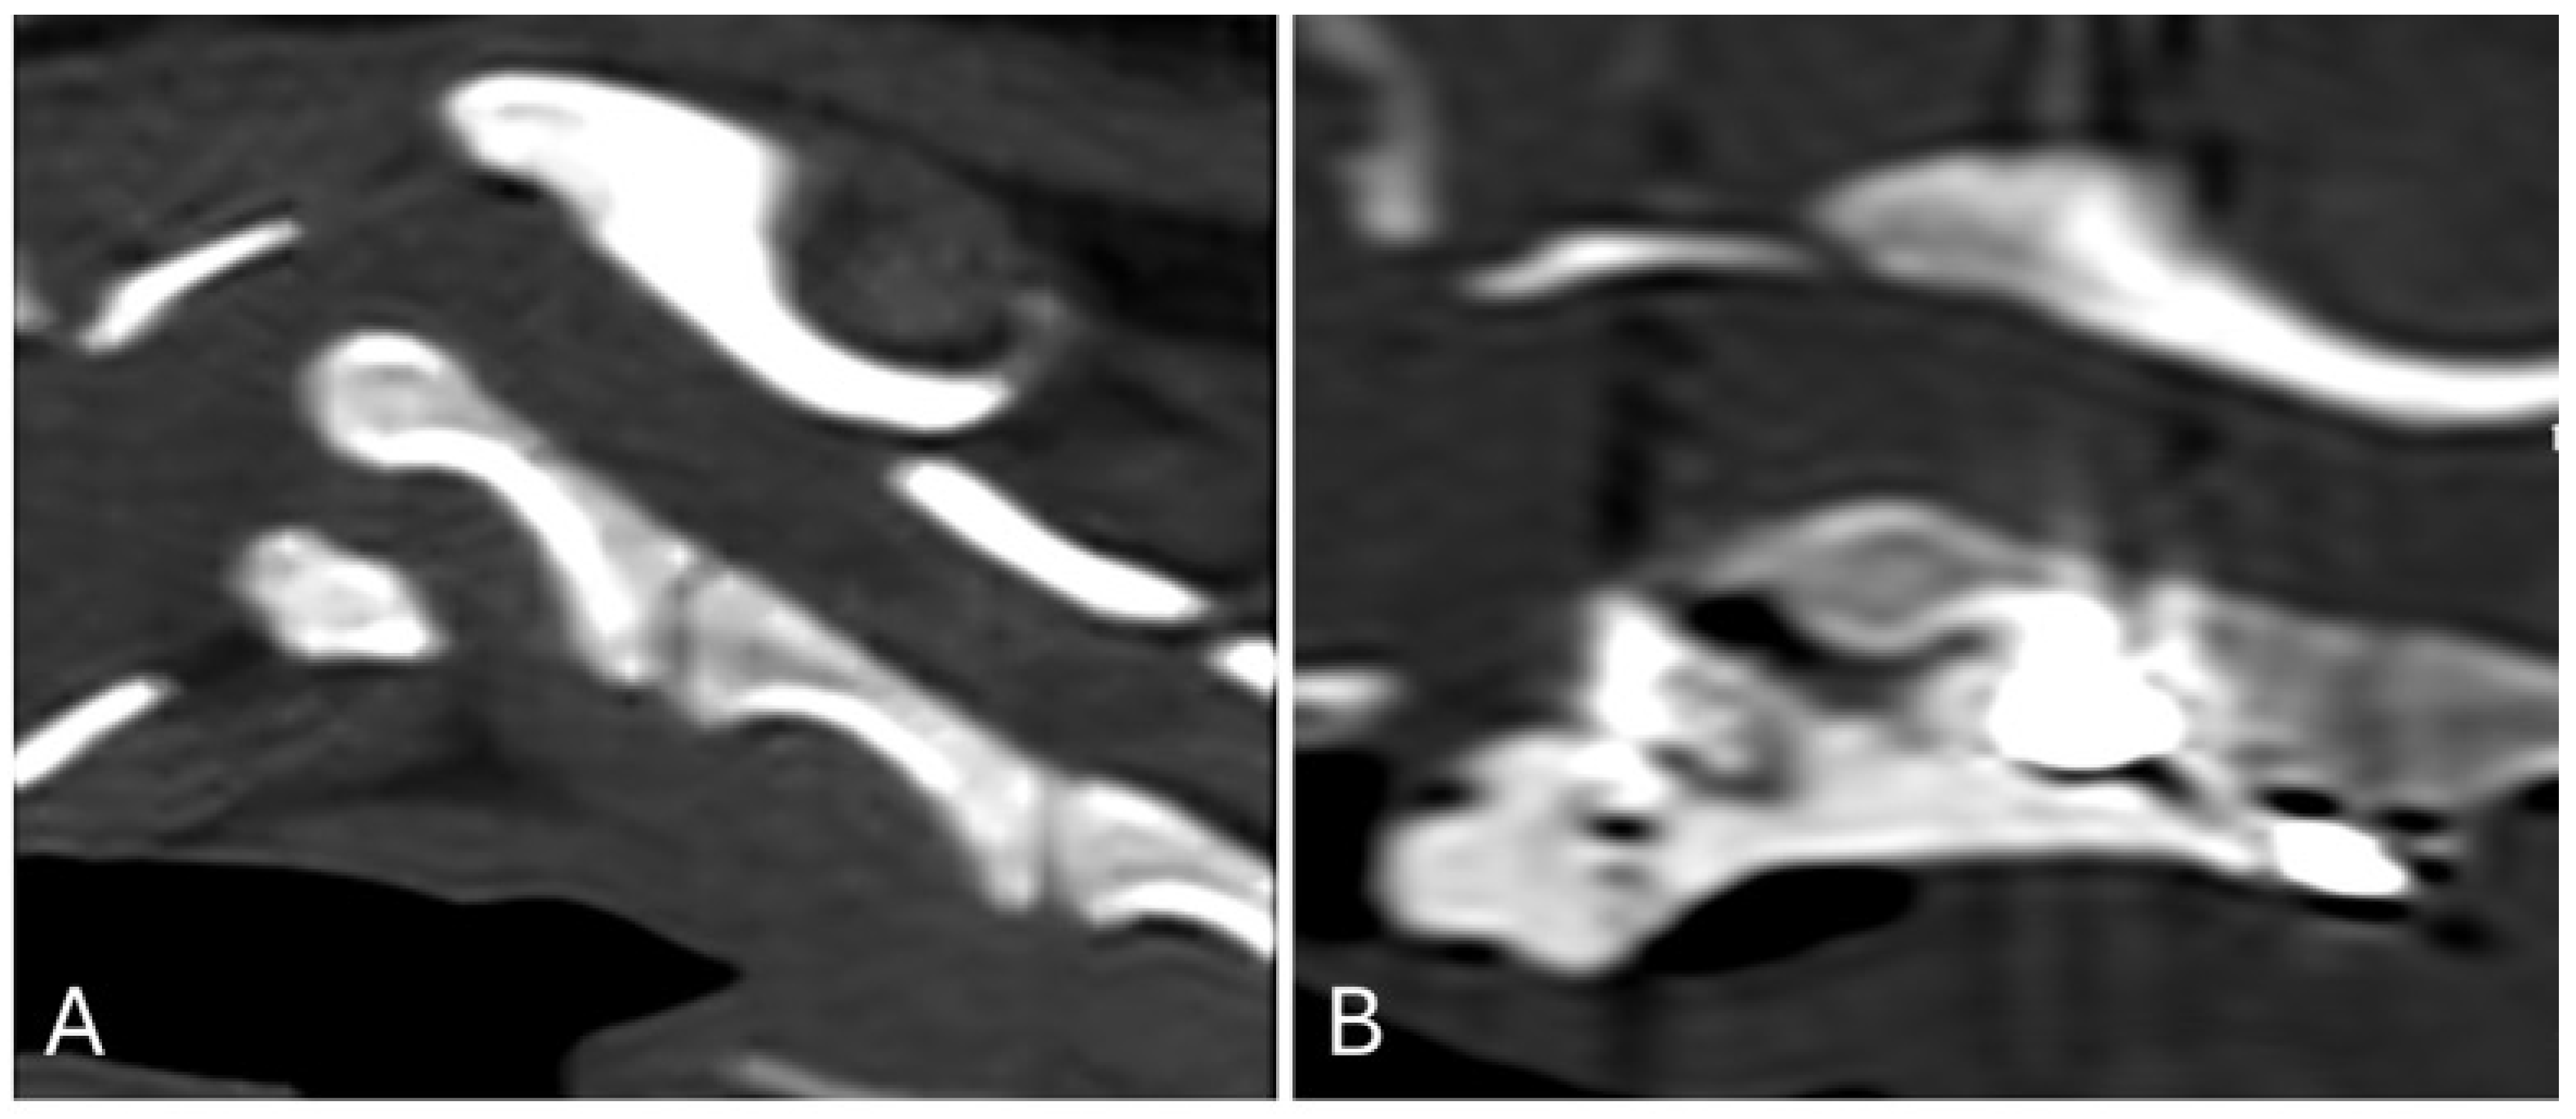

Radiographs of the cervical spine were taken in latero-lateral projection, with the spine in a neutral position and parallel to the X-ray table, and with the cervical spine positioned directly under the primary X-ray beam. Three radiographic morphological indices were assessed on cervical radiographs: the ventral atlantodental interval (VADI), the dorsal atlantodental interval (DADI), and the C1–C2 overlap. The VADI was measured by drawing a line perpendicular to the longitudinal axis of the dens of C2, extending from the dorsal part of the ventral arch of C1 and ending at the ventral aspect of the dens of C2. The DADI was measured with a line perpendicular to the longitudinal axis of the dens but extending from the ventral part of the dorsal arch of C1 and ending at the dorsal aspect of the dens of C2. The ventral compression index (VCI) was calculated as the ratio of the ventral atlantodental interval (VADI) to the dorsal atlantodental interval (DADI) (VADI/DADI) (Figure 1A). The C1–C2 overlap was determined by measuring the distance between two lines, both perpendicular to the longitudinal axis of the dens of C2, the first tangent to the caudal border of the dorsal arch of C1, and the second tangent to the cranial border of the spinous process of C2 (Figure 1B).

Figure 1. Neutral lateral radiographic projection of the atlantoaxial joint: ventral atlantodental interval (VADI) (blue line) and dorsal atlantodental interval (DADI) (green line) (A); line tangent to the caudal border of the dorsal arch of C1 (green line) and line tangent to the cranial border of the spinous process of C2 (blue line) (B).